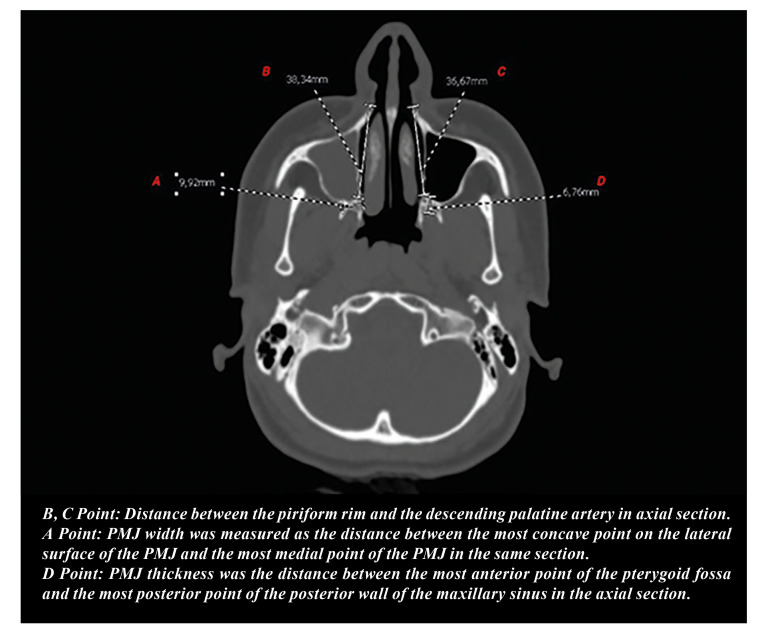

Material and methods: This prospective, controlled, randomized study included forty-three patients were randomly assigned to either the conventional or customized (study) osteotomy groups. In the study group, LNW depth was measured before surgery in the axial section of the CT scan, and LNO was performed at a depth of 2 mm less than the measured distance. In the conventional osteotomy group, LNO was performed at 30 mm for females and 35 mm for males. Patients with cleft lip and palate, previous orthognathic surgery, or rhinoplasty were excluded. Separation types were classified as follows: LNW types; Type1-from the osteotomy line; Type2- 2-4 mm above the osteotomy line; Type3- 4 mm or more above the osteotomy line. PMJ types; Type1-including the tuber maxilla; Type2-from the pterygomaxillary junction; Type3-including the pterygoid plates. Chi-square tests were conducted to determine whether there was a significant correlation between groups and LNW separation types, groups and PMJ separation types and groups, and LNW separation type and PMJ separation type. A P value of < .05 was considered statistically significant.